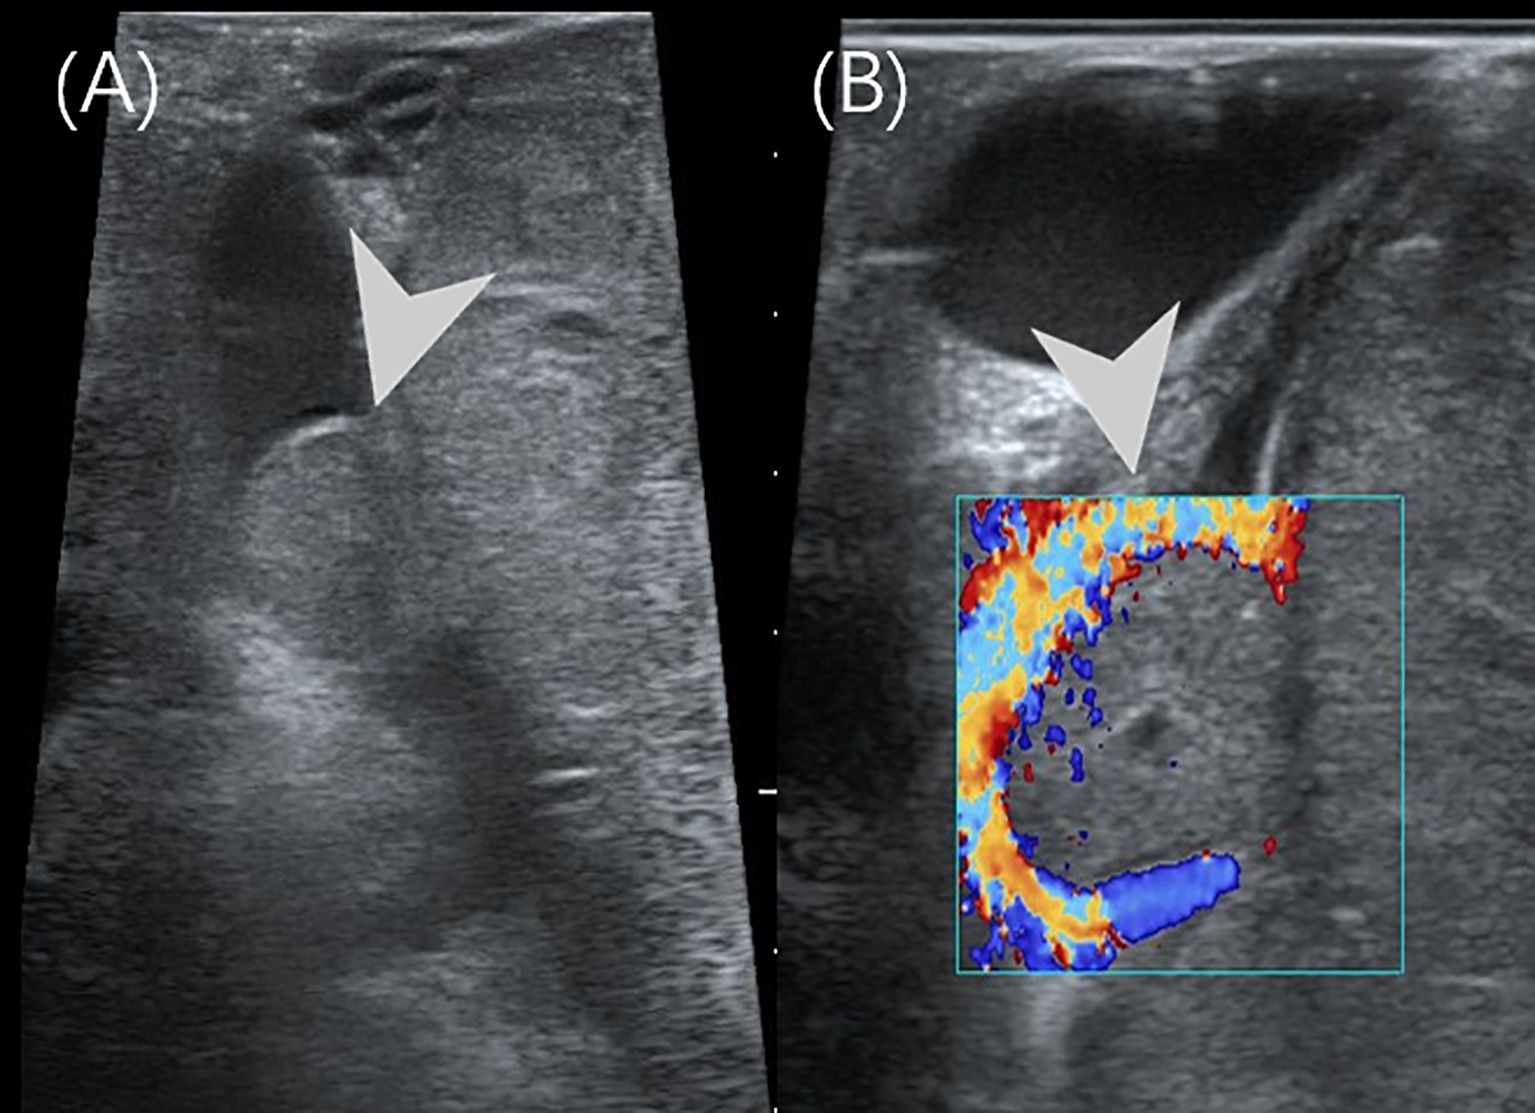

Pancreatoblastoma (PB) is a rare malignant neoplasm of the pancreas, primarily affecting children. While some reports have described the imaging characteristics of PB, detailed descriptions of its ultrasound (US) and contrast-enhanced ultrasound (CEUS) features in children are limited. We reported two cases of PB admitted to our hospital with detailed ultrasonographic features. The first case involved a 14-year-old girl who presented with intermittent, unexplained epigastric pain. CEUS revealed a hypoechoic mass with heterogeneous hyperenhancement in the pancreatic head. She underwent pancreaticoduodenectomy and remains disease-free to date. The second case was a 4-year-old boy with a palpable, unexplained mass in the right upper abdomen. US identified a well-defined, heterogeneous mass in the epigastric region with internal point-like hyperechoic areas. The intraoperative US showed portal vein cancer thrombus. He underwent tumor resection along with reconstruction of the portal and superior mesenteric veins. He subsequently received chemotherapy and remained disease-free to date.